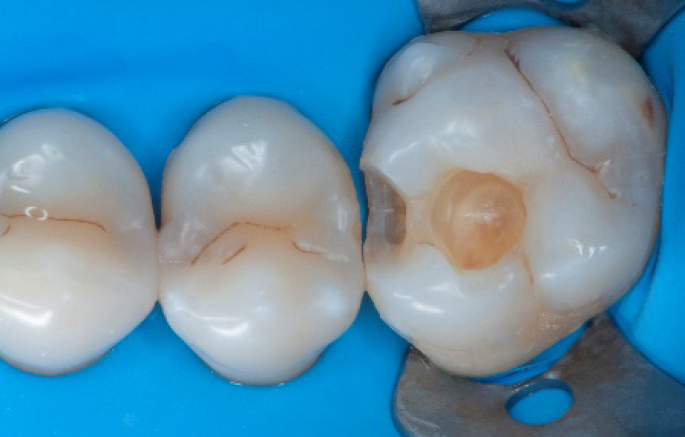

Step 9:

Transformation of a big class I into a small class I, using SDR® flow+ material in one increment up to 4 mm.

Step 10:

The situation after the application of SDR® flow+ material.

Step 11:

Occlusal surface restored using Spectra ST4 composite in shade A2.

Step 12:

The situation after rubber dam removal.

Step 13:

Occlusal check

Step 14:

2 weeks control